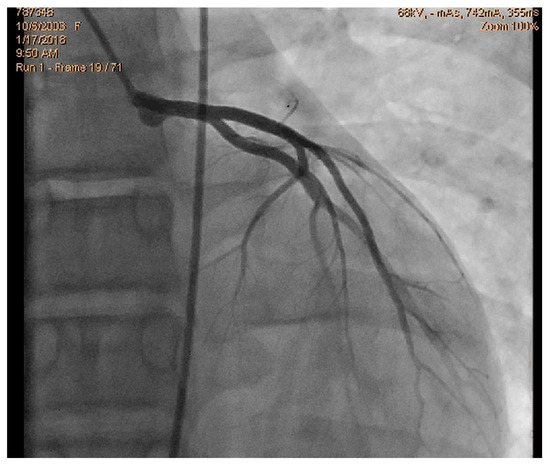

We read with interest the excellent review manuscript from Huang, S.-W. and Liu, Y.-K. [1], which describes that pediatric chest pain is a common chief complaint in the emergency department. Not surprisingly, children with chest pain are usually brought to the emergency department by their parents out of fear of heart disease. However, chest pain in the pediatric population is generally a benign disease. In this review, we have identified musculoskeletal pain as the most prevalent etiology of chest pain in the pediatric population, accounting for 38.7–86.3% of cases, followed by pulmonary (1.8–12.8%), gastrointestinal (0.3–9.3%), psychogenic (5.1–83.6%), and cardiac chest pain (0.3–8.0%). Various diagnostic procedures for cardiac chest pain are commonly used in the emergency department, including electrocardiogram (ECG), chest radiography, cardiac troponin examination, and echocardiography. However, these examinations demonstrate limited sensitivity in identifying cardiac etiologies, with sensitivities ranging from 0 to 17.8% for ECG and 11.0 to 17.2% for chest radiography. To avoid the overuse of these diagnostic tools, a well-designed standardized algorithm for pediatric chest pain could decrease unnecessary examination without missing severe diseases [2,3,4]. Our primary concern is that no attention has been given to exercise-induced intraventricular gradients, which are easily detectable using exercise stress echocardiography and have been associated with chest pain and other symptoms [5,6,7,8,9,10,11,12,13], including in children. We present the case of a 15-year-old boy, a rugby player, who experienced severe chest pain followed by syncope during a match. Upon evaluation at the emergency department, he showed a significant increase in troponin levels. Coronary angiography (Figure 1) and CT angiography (Figure 2) revealed normal results. However, an exercise stress echocardiogram identified a significant intraventricular gradient (Figure 3).

This was considered the most likely cause of the clinical event. This test was repeated under bisoprolol therapy. In our experience with 139 athletes [11], 58 (41%) were under 18 years old—46 of whom were evaluated for exercise-related symptoms—and 20 (34%) developed an intraventricular gradient during exercise. We strongly advocate for exercise stress echocardiography to be considered for children presenting with exercise-related symptoms in the emergency department at the appropriate time. According to our experience [8], approximately 40% of children with clear exercise-related symptoms, like angina, dizziness, syncope, ST alterations in ECG, or ST alterations in exercise stress ECG (Figure 4), develop mid-ventricular obstruction (MVO) (Figure 5), which appears to be a relatively high prevalence; we recognize this warrants further explanation regarding the mechanisms of development and relationship to chest pain.

In our experience and in the literature [5,6,7,8,9,10,11,12,13,14,15,16], chest pain (exercise angina) has been related to an anatomically small LV chamber, small LVOT, and to an increased relative wall thickness. Additionally, a certain level of hypohydration—characterized by a reduction in left ventricular volumes and commonly linked to intense exercise—may be a potential contributing factor to MVO.As most of the children were referred by other centers, these children were not systematically followed up longitudinally. However, it is our knowledge that four have participated in the genetic study for myocardiopathy and one developed HCM [10]. The increase in intraventricular pressure causing perturbation in subendocardial perfusion is the potential mechanism for ischemia, chest pain, and ST alterations [15,16]. Furthermore, using beta-blockers in children without structural cardiac abnormalities remains a controversial approach. The use of beta-blockers [17,18] is recommended and suitable for pediatric arrhythmias, hypertension, heart failure, hypertrophic cardiomyopathy, migraine prophylaxis, hyperthyroidism, and infantile hemangiomas. Beta-adrenergic receptor antagonists, commonly known as beta-blockers, are divided into three generations based on their receptor selectivity. First-generation beta-blockers (e.g., propranolol) are non-selective and block both β1 and β2 receptors. Second-generation beta-blockers (e.g., metoprolol) are relatively selective for the β1 receptor, while third-generation beta blockers (e.g., carvedilol) block β1, β2, and α1 receptors. Beta-blockers are frequently used to treat adult cardiac conditions, such as hypertension, atrial arrhythmias, and chronic heart failure. Similarly, they are considered a first-line treatment for many pediatric tachyarrhythmias, both in non-operative and peri-operative settings [19]. However, despite their widespread use in children, there is a significant lack of pediatric-specific data to determine precise dosing and personalized treatment. As a result, most pediatric treatment decisions are based on data extrapolated from adult studies. The most commonly prescribed oral beta-blockers for children include atenolol, carvedilol, metoprolol, propranolol, and bisoprolol [19]. The use of beta-blockers is recommended for adult patients with exercise-induced IVPG, whether or not they have hypertrophic cardiomyopathy [20,21,22,23,24]. Based on both our findings and the existing literature, we suggest that children would also benefit from the same treatment (Figure 3).

Figure 3. An intraventricular-induced gradient in one child with chest pain followed by syncope during a rugby match. In the upper image, there is a huge intraventricular gradient and in the lower image, there is a small intraventricular gradient under treatment with bisoprolol.